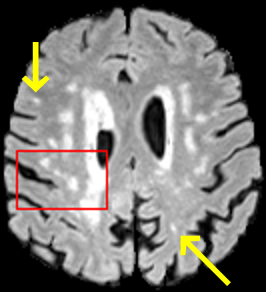

To test the impact of the iterative refinement on YODA’s translation quality, we compared regression and diffusion sampling on the RS data and present additional generation examples in Fig. 6. We observe that diffusion sampling visually resembles the appearance of the acquired images. Regression sampling preserves key anatomical features – the GM/WM boundary, WMHs (Fig. 4), the outline of the pallidum (Fig. 6) – but omits many high-frequency features. To investigate whether iterative refinement during diffusion sampling adds relevant and systematic medical information or only imitates acquisition noise, we performed ExpA sampling, i.e. averaging the output of several ( or ) diffusion trajectories. We observed a gradual loss of high-frequency details when increasing the (see also the supplementary video), indicating that the effect of the iterative refinement is non-systematic. For , the images are visually almost indistinguishable from the initial regression solution (see the supplementary video, and Fig.4 and 6). We directly compared the synthesis results of ExpA () and regression sampling quantitatively and found the differences to be minimal (SSIM: 99.73%, PSNR: 45.30 dB), i.e. diffusion sampling approaches the initial regression solution for a high . The quantitative analysis of the image quality (Tab. 1) showed that diffusion sampling impairs the assessed SSIM and PSNR in comparison to regression sampling for both the in- and external test sets, which we attribute to noise generation (Sec. 3.1). In turn, ExpA averages improved both metrics and, for , performed mostly on par with the regression solution in both test sets in terms of SSIM, while the PSNR in the RS was slightly increased (Tab. 1). However, we observed that ExpA sampling YODA improves the replication of systematic 3D low-frequency image intensity drifts (bias fields) due to the 3D synchronization in 2.5D diffusion sampling. Yet, this apparent advantage did not generalize to the external MBB dataset, as bias fields are MR protocol-specific.

We evaluated the impact of the proposed sampling methods on the performance of the independent, externally trained SHIVA-WMH tool as compared to manual reference labels (Tab. 1). Smoother images (higher or from regression sampling) yielded improved performance over those from diffusion sampling.

To assess the suitability of YODA-generated images for WMH detection independent of segmentation tools, we also calculated the CNR (15) of WMHs. This confirmed that the contrast of WMHs is preserved in the regression images, whereas we noted slightly reduced WMH contrast for diffusion and ExpA-sampled images (Tab. 1).

When analyzing the RS synthesis results (Fig. 4), we noted that most reference methods strive to imitate realistic images, but several artifacts can be observed such as hallucinated WMHs (SynDiff) and salt-and-pepper noise (SynDiff, I2I-Mamba, ResViT).

Furthermore, our analysis underlines that pure intensity-based performance metrics are a faulty indicator of WMH translation quality, as e.g., the Ea-GAN achieved competitive SSIM and PSNR, but WMH translation was poor (Tab. 1).